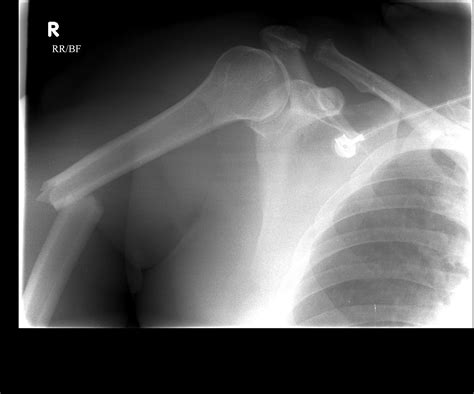

Diagnosing Proximal Humerus Fractures

Diagnosing a proximal humerus fracture involves a combination of physical examination and imaging tests. The diagnostic process typically includes:

• Imaging Tests: X-rays are the primary imaging tool used to diagnose proximal humerus fractures. In some cases, additional tests such as CT scans or MRIs may be ordered to provide more detailed images.